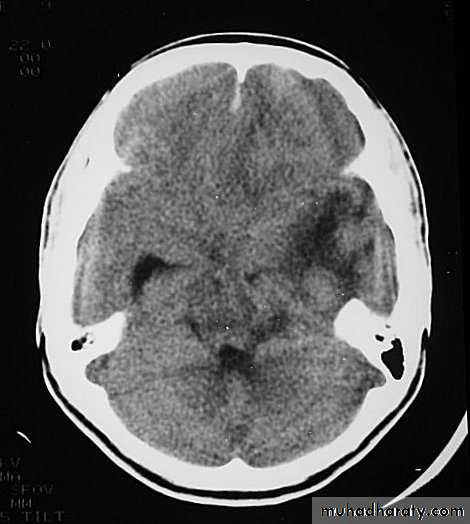

1. Brain Oedema (Cerebral Swelling)

Can be local (around a haematoma) or diffuse.

It is due to intracellular or extracellular accumulation of fluid.

It leads to raised intracranial pressure, which itself causes problems.

It is more common and more dangerous in children.